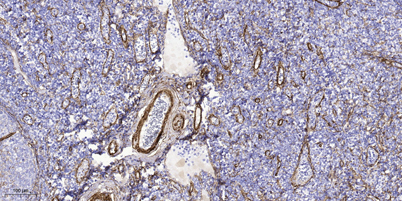

Product name: CARD 10 rabbit pAb

Dilutions: Western Blot: 1/500 - 1/2000. Immunohistochemistry: 1/100 - 1/300. Immunofluorescence: 1/200 - 1/1000. ELISA: 1/10000. Not yet tested in other applications.

Cellular localization: Cytoplasm .